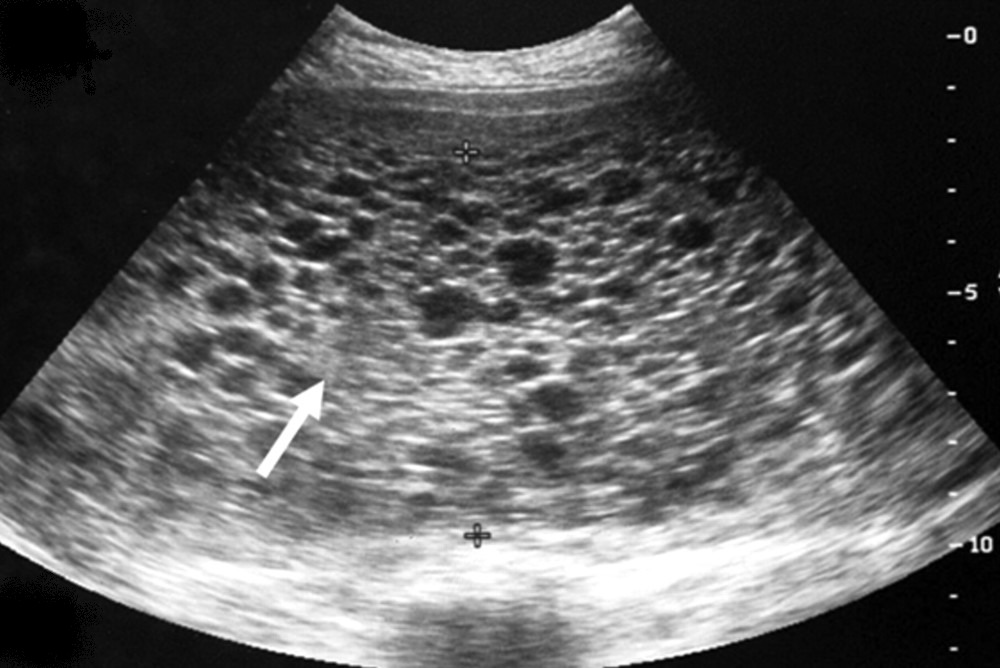

Bij het PolyCysteus Ovarium Syndroom ontstaan in beide eierstokken (ovaria) ronde, dunwandige met vocht gevulde